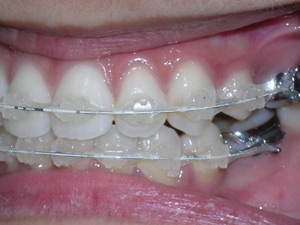

Here are the porcelain braces applied.